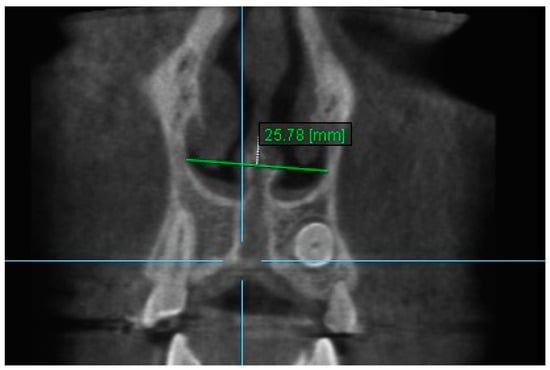

10. Aperture of Midpalatal Suture 10: The distance between the inner points of posterior median palatine suture, bilaterally in posterior nasal spine (PNS) (Figure 12).

Figure 12.

Aperture of Midpalatal Suture 10.

Statistically significant differences were found between the mean value of Apertures of Midpalatal Sutures 10 and 11 between all the time intervals, i.e., between T2–T1, T3–T1 and T3–T2 (p < 0.005). An increase in the mean values of Apertures of Midpalatal Sutures 10 and 11 were observed immediately after the end of RPE (T2–T1). Statistically significant decreases were found 6 months after RPE (T3–T2). The overall (T3–T1) differences between pre-expansion and 6 months after expansion for Apertures of Midpalatal Sutures 10 and 11 were found statistically significantly increased (Table 11 and Table 12).

Table 11.

Results of the mean differences (mm) of Aperture of Midpalatal Suture 10 in the three time intervals.

The results of this study show that the expansion of the maxilla, shown at the aperture of the midpalatal suture, has a triangular pattern. It was found that the amount of increase was greater (a) at the anterior median palatine suture, (b) bilaterally in the inferior alveolar ridge of the central incisors than the posterior, and (c) bilaterally in at posterior nasal spine (PNS). Similar results to our study have shown that the midpalatal suture has a triangle shape, with the triangle’s vertex in the PNS and its base in perspective [1,2,36,37]. According to Da Silva et al. [38], the palatal suture has its largest width in the anterior region and does not have a parallel opening configuration in the axial plane. Additionally, Kartalian et al. [39] found that after RPE, the midpalatal suture separates in a nonparallel manner in response to expansion forces. The maxilla articulates with unpaired bones, which limits the amount of separation. Caldas et al. [40], studying the effect of rapid maxillary expansion on the nasal cavity assessed with cone-beam computed tomography, concluded that there is a great transverse movement and subsequent separation of the nasal conchae from the nasal septum in both the anterior and posterior sections of the inferior portion of the lateral walls of the nasal cavity after RPE.

During the retention time between the end of RPE and 6 months post-expansion (T3–T2), a decrease in all variables was found. According to Ballanti et al. [35], after a 6-month retention period, the midpalatal suture lost 89.55 and 77.78% of its increased area at the anterior nasal spine (ANS) and the posterior nasal spine (PNS), respectively. They believed that after the 6-month retention period, the midpalatal suture looked restructured with a transverse dimension equivalent to the pre-treatment width. In the present study, after 6 months retention the midpalatal suture lost 54.485% at ANS and 36.842% at PNS, respectively.